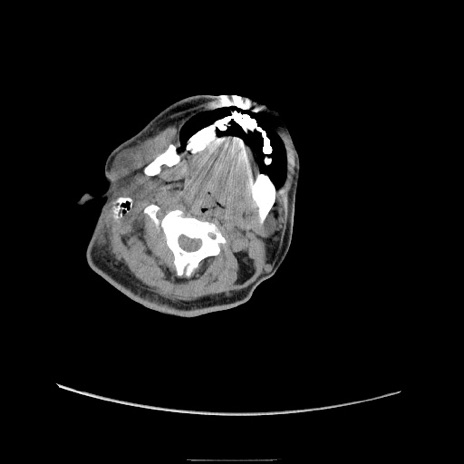

冠状断像

【症例】50歳代男性

【主訴】腹痛

【現病歴】AVMからの被殻出血のため回復期リハ病棟入院中。 本日午後3時頃急に下腹部痛が出現した。

【既往歴】AVM、被殻出血、虫垂炎、高血圧

【身体所見】意識晴明、左半身不全麻痺、会話の理解は良好、36.5°C、腹部:膨隆、全体に板状硬、下腹部正中に圧痛点あり、反跳痛-、筋性防御不明、右下腹部にope scar

【データ】WBC 9400、CRP 0.06